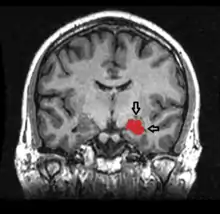

![]() قرن آمون (البصلة الوردية السفلى) كجزء من الجهاز الطرفي قرن آمون (البصلة الوردية السفلى) كجزء من الجهاز الطرفي | |